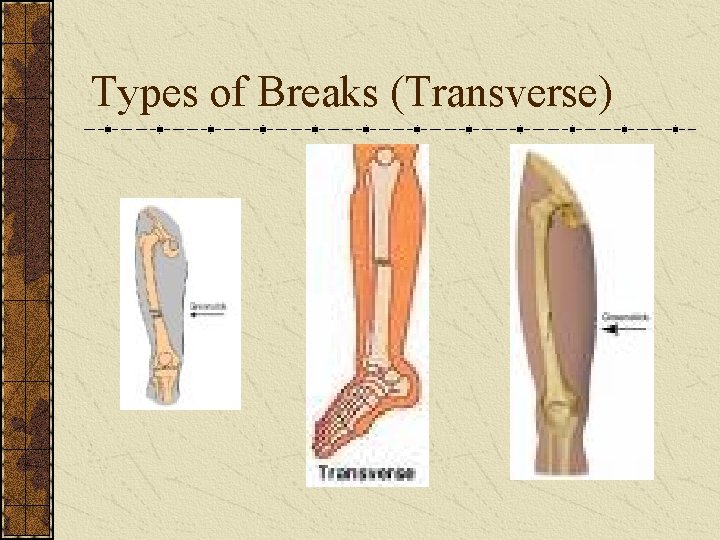

Types of Breaks There are five different types of fracture: 1. Transverse: Straight across bone 2. Oblique: Diagonal break across bone 3. Spiral: Around the bone 4. Comminuted: Bone is shattered 5. Greenstick: Bone breaks like a stick

Types of Breaks (Transverse)